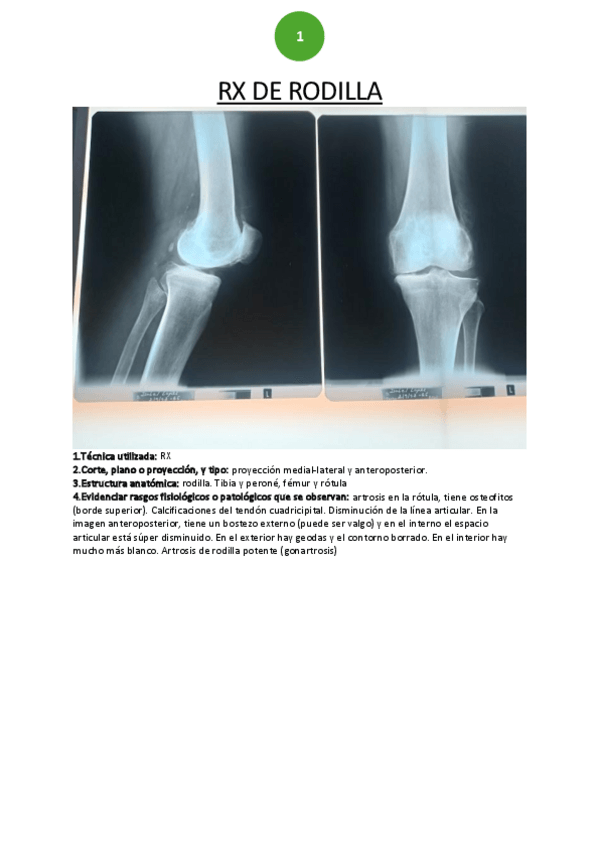

He publicado nuevos practicas de 2º Fisioterapia en Especialidades Clínicas II: RX-rodilla.pdf

13 páginas